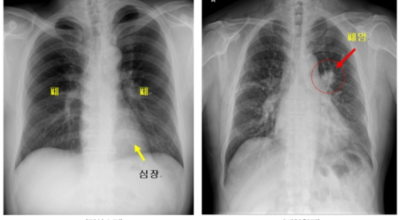

폐암 검사는 주로 X-ray를 통해 이루어지지만, 종양의 크기가 작거나 구석에 위치한 경우에는 확인이 어려운 경우도 있습니다. 그 후, 조직 검사를 통해 정확한 진단을 하게 됩니다. 폐암이 발견되면, 종양의 크기, 전이 여부, 위치에 따라 수술 여부를 결정하게 됩니다.